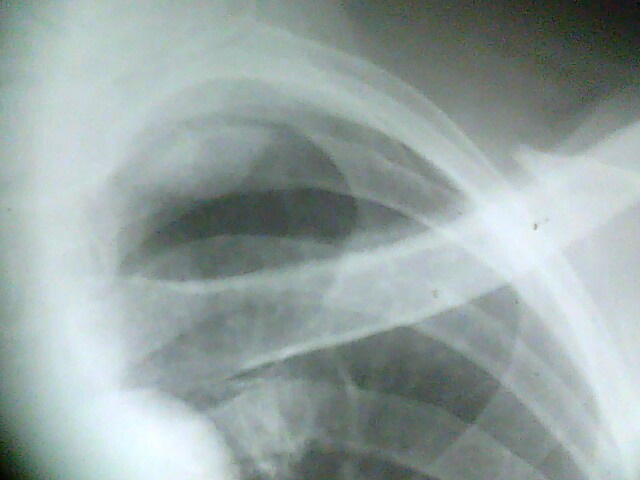

标题: X4925:胸片:男54岁。常规检查

男54岁。常规检查 。给病人透视了一下,这个位置侧位看不到。还是考虑你胸膜病变。已建议ct,有结果我会发上来。

左肺尖病灶:首先考虑肺上沟癌,其次左上纵隔肿瘤。

左上胸膜肿瘤。

没有侧位片,从正位片上可知气管未受压,考虑为来自后纵隔或胸膜的良性肿瘤.

气管似略右移,病变位于主动脉水平以上,首先排除胸内甲状腺

既然是常规检查,肯定没有临床指征,考虑肺顶胸膜局限性增厚,建议ct以除外占位。

这个病人做了ct,追踪时已经出院,没看到结果和片子。病历上写的是:ct报的是左胸廓入口占位,建议颈部和胸部增强扫描。但据说病人不愿意增强,已经出院。